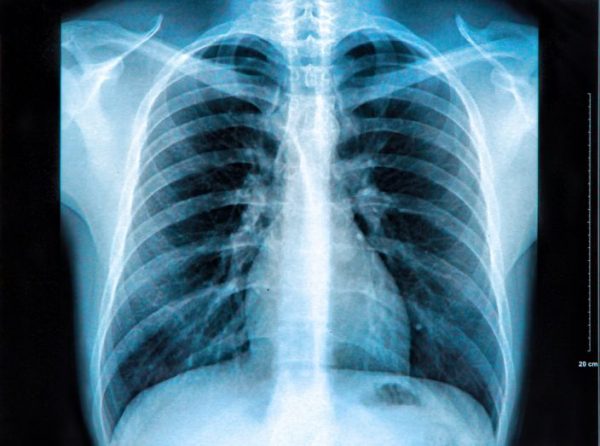

Fue al realizarse esta prueba cuando detectaron un objeto “metálico lineal” en su corazón. Calcularon que medía alrededor de 3,5 centímetros de largo y que un parte sobresalía del ventrículo izquierdo. Lo que no lograban averiguar es cómo había llegado hasta allí. Ni siquiera el propio paciente lo sabía.